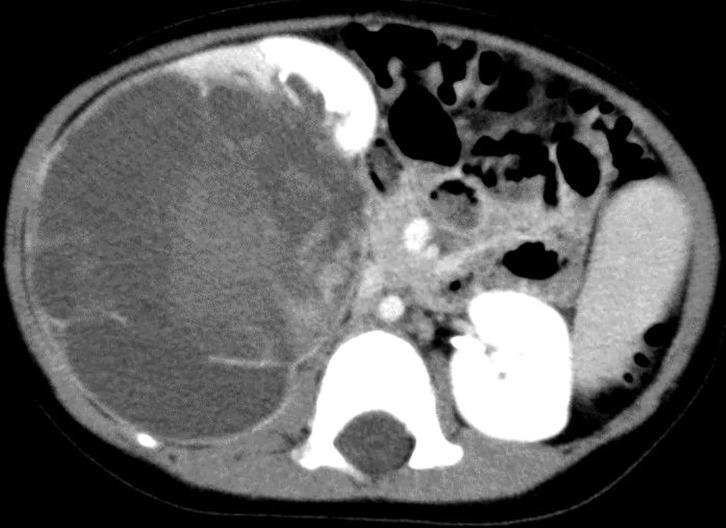

一名既往健康的2岁女孩出现肉眼血尿和右腹部肿块。她有肿瘤家族史;她的大姨患横纹肌肉瘤,另一位大姨患滤泡性甲状腺癌,她的外祖母患良性甲状腺肿瘤。影像学检查显示右肾有一个10厘米的肿瘤,内部有明显的囊性结构。患者接受了右肾切除术,切除了一个大小为12.5×9×8厘米的肿瘤,该肿瘤包含囊性和实性部分。肿瘤由具有间变改变的梭形细胞组成。最终,确诊为ASK。按照肾透明细胞肉瘤或弥漫性间变型威尔姆斯瘤的治疗方案进行治疗。基于ASK的诊断和相关肿瘤的家族史,怀疑为综合征。使用肿瘤标本对热点区域(即核糖核酸酶IIIb结构域)进行测序,并使用血液样本对基因的编码区域进行测序,结果显示体细胞突变c.5125G>A(p.D1709N)和种系突变c.4458dupA(p.S1487Ifs*5)。治疗结束至今已过去两年,患者存活且健康,无肿瘤复发迹象。